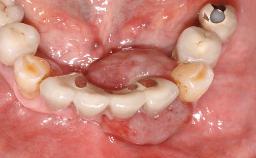

Surgical treatment of a 67-year-old male patient exhibiting an extended edentulous space in the anterior maxilla after the removal of three hopeless incisor teeth.

The video demonstrates implant placement using a surgical stent according to the principle of prosthodontically driven implant placement. The deficient ridge is augmented with locally harvested autologous bone chips, a superficial layer of xenogenic DBBM particles and a resorbable collagen membrane. The surgery is completed with a precise, tension-free primary wound closure.

The case concludes with the presentation of the final prosthesis and the esthetic outcome, demonstrating stable soft tissue conditions and stable bone crest levels at the 3-year follow-up.

# of Teeth 4

# of Implants 2

Prosthesis Type FDP